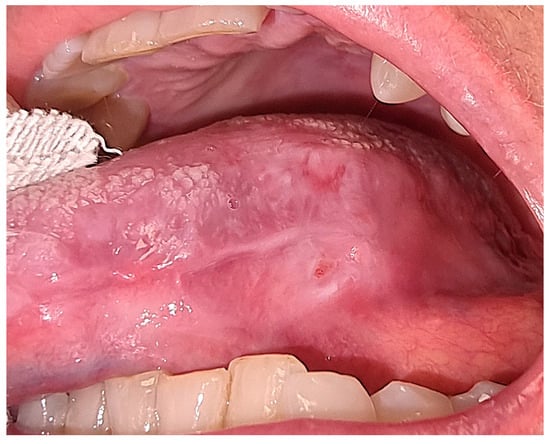

After three sessions, we achieved complete healing of the lesion and the remission of signs and symptoms (Figure 5).

Figure 5. Intraoral aspect of the affected tongue area at the end of treatment, showing the healing.

A maintenance therapy consisting of a chlorhexidine 0.2% mouthwash for oral antiseptic and a hyaluronic acid gel was prescribed, and the patient began the follow-up period. During the follow-up visits, the clinical picture remained stable, and after one year, there were no signs of recurrence of the condition.